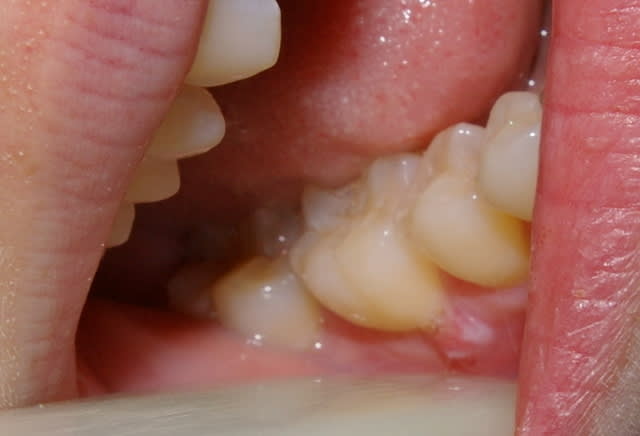

patiente genée par protub gingivale, pas de douleus, hygiene impeccable, pas de cause decelée, quoi faire?antiseptiques locaux, eviction et greffe?

... on ne voit pas bien, mais ça ne serait pas plutôt un papillome?

exerese - analyse. Sans doute un papillome

modalités de l'exerese, inclinaison de la lame, largeur du prelevement, remplacement des tissus enlevés?